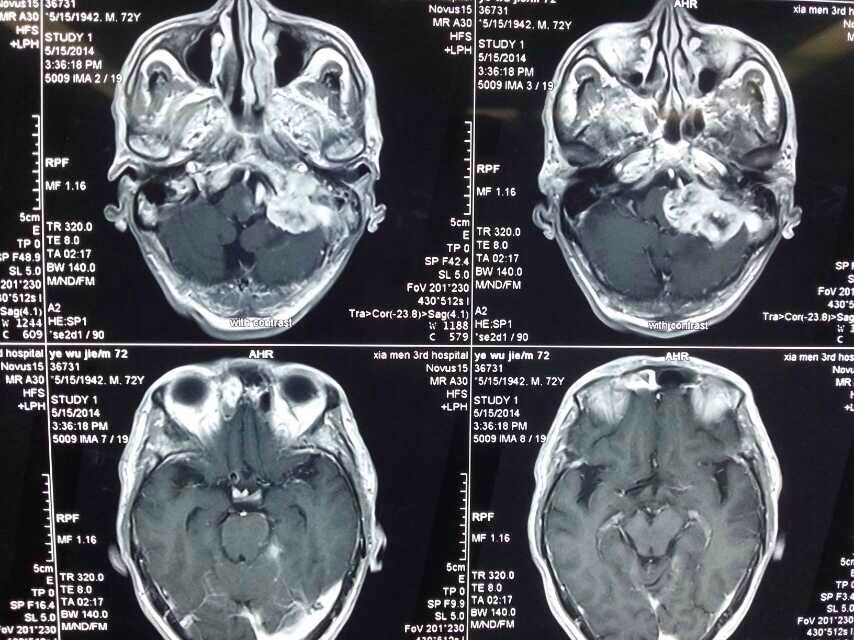

2014520是个特别的日子,第三伦理片 手术室灯火通明,神经外科调集所有的技术团队手术一台接一台,有脑动脉瘤破裂的,有脑外伤出血的,忙碌不停。